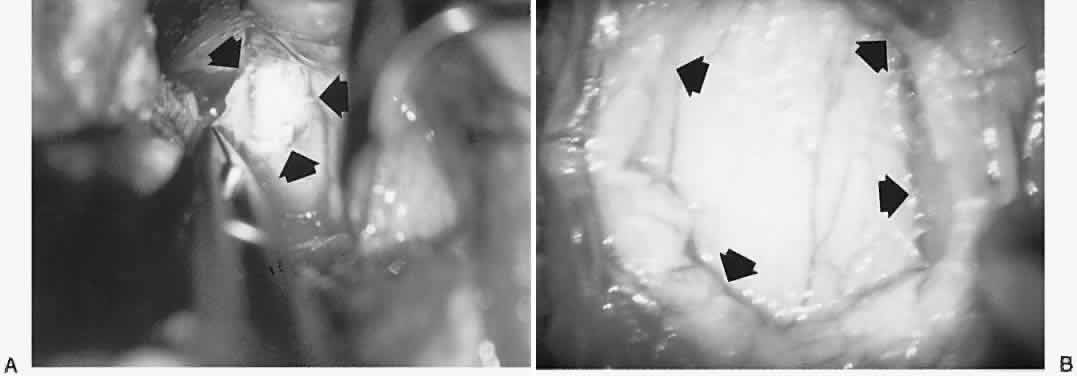

Abnormalities of the conjunctiva may serve as clues to orbital diagnosis. In general, edema (chemosis) is too nonspecific a finding to be very helpful, being common in Graves' disease, inflammatory pseudotumor, and arteriovenous fistulas. Any retrobulbar mass may produce chronic or intermittent chemosis, presumably by interfering with venous drainage in the orbit. In Graves' ophthalmopathy, the vessels overlying the insertions of especially the medial and lateral recti muscles are commonly enlarged, and indeed the muscle insertions themselves may be visibly hypertrophied (Fig. 5). These two conjunctival signs are exceedingly useful in identifying Graves' orbitopathy and should be sought in cases of unexplained proptosis and/or diplopia. Also, engorgement of orbital vessels may be reflected as hypervascularity of conjunctival and scleral vessels, which take on a more-or-less specific pattern in the presence of arteriovenous fistula (see Volume 2, Chapter 17, Fig. 14).

Fig. 5. Conjunctival signs of Graves' congestive orbitopathy. A. Characteristic fleshy hypertrophy of insertion of right lateral rectus (large arrows). Note localized chemosis of left caruncle (small arrow). B. Hypertrophy of insertion of medial rectus with hypervascularity of the vessels overlying the horizontal recti insertions (arrows).